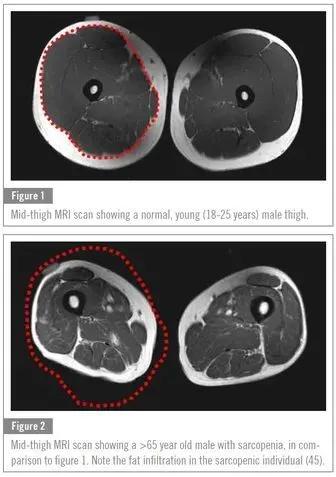

02 肌少症

肌少症,顾名思义就是 肌肉质量减少,肌肉力量减退 。肌少症的一个重要病因是蛋白质摄入不足。有很大的潜在危险,老年人患肌少症会导致肌肉力量严重下降, 跌倒、骨折、骨质疏松、骨关节炎 等发生率都会随之大大增加。

上图为18~25岁年轻男性肌肉量

下图为65岁以上患肌少症老人的肌肉量

而肉类是很重要的 蛋白质来源 ,如果长期不吃肉,又没有通过其他方式进行补充,生病的风险会大大增加,老年人尤其如是。